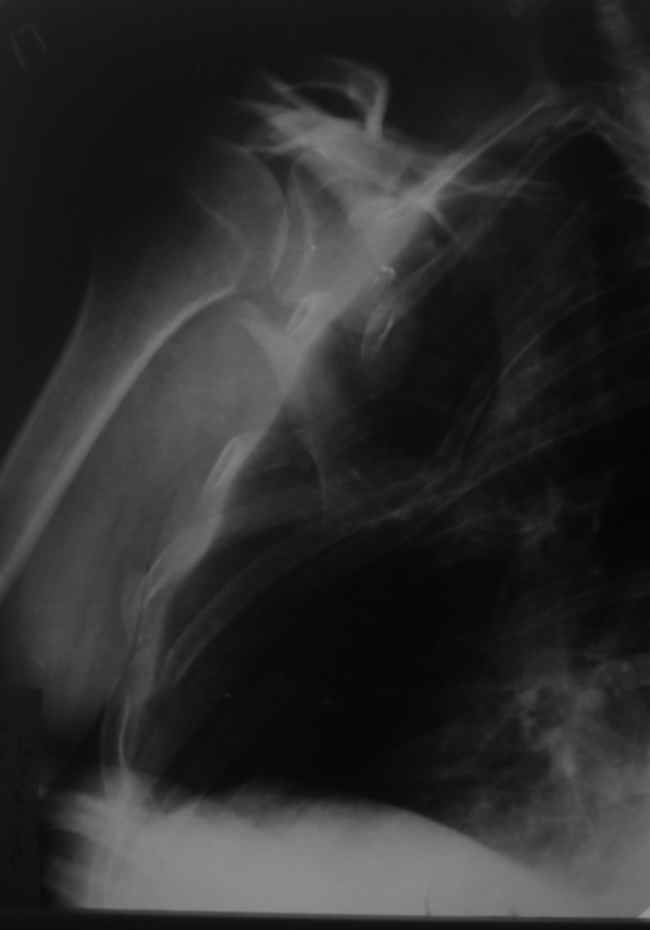

Уважаемые коллеги, помогите определиться с тактикой. Больной 1953гр, травма на стройке, придавило тяжелымпредметом. Сейчас в сознании, стабилен, плевральная полость задренирована. Предполагаем синтез ключицы, если бы не переломы ребер, установили бы шину ЦИТО.Есть у кого опыт открытого/закрытого синтеза подобной лопатки? Что делать с клювовидным отростком? Спасибо, Моисеев Ю.И.